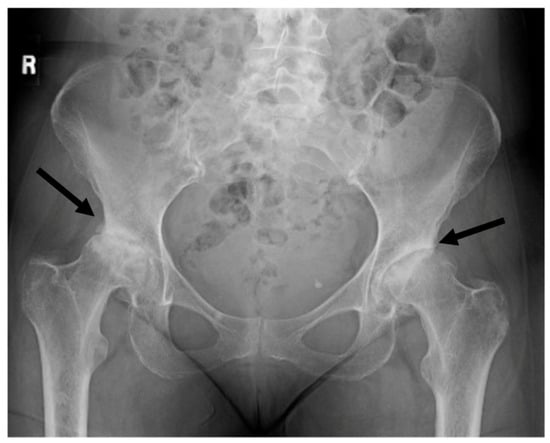

The community of progressive physicians who work to help such patients are familiar with the lack of accurate diagnostic techniques for vector-borne disease and often empirically treat based on clinical presentation. Based on her symptoms consistent with Bartonella infection, the patient was prescribed clarithromycin and rifampin treatment based on the known antibiotic sensitivity of Bartonella []. Despite these antibiotics, she continued to decline. Due to ongoing neurological symptoms, her primary care clinic referred her for evaluation at clinics specializing in multiple sclerosis (MS) and amyotrophic lateral sclerosis (ALS), both of which were ruled out. She was then offered psychological counseling and physical therapy. Her physical therapist recommended a wheeled walker in the summer of 2020. In October of 2020, she was told that she should think about taking a vacation with family as she probably would not be able to do so in the future. She reported to multiple physicians that her hips sounded like popcorn whenever she walked or climbed stairs. In early 2021, her physical therapist recommended she use a wheelchair. At this point, her primary care doctor ordered hip X-rays (Figure 2).

Figure 2.

X-rays taken in the spring of 2021, two and a half years after the spider bite. No symptoms of arthritis had been observed prior to this event and the patient had been followed closely for signs of arthritis due to her family history and her participation in a long-term research study for the risk of rheumatoid arthritis. Arrows indicate joint space narrowing indicating loss of cartilage.

The X-rays revealed bilateral hip degeneration which required surgical replacement of the joints. Prior to surgery, she submitted a blood sample to TLab Inc. for Bartonella henselae rRNA FISH molecular testing with enhanced sensitivity using a confocal microscope system (Figure 3).